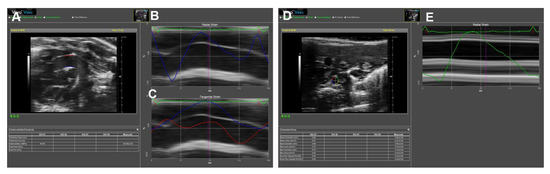

M-mode ultrasonography detects the structures along a single axis, by which the tissue interfaces are represented in dots on the display screen. With a high temporal resolution, M-mode images can measure the inner diameter and wall thickness of the aorta from several cardiac cycles. Thus, systolic and diastolic diameters could be obtained simultaneously [29]. As illustrated in Figure 2, an M-mode line can be placed perpendicular to the aortic walls, such as a long-axis view of the AAo (Figure 2A,B) and a short-axis view of the DAAo (Figure 2C,D). The image acquisition of the aorta by M-mode ultrasonography and its application in assessing aortic dimensions are similar between humans (Figure 2A,C) and rodents (Figure 2B,D).

Figure 2. Representative M-mode displays of the aorta for the anterior–posterior diameter measurement. (A,B): The long-axis view of the ascending aorta (AAo) obtained in systole and diastole in human (A) and mouse (B). (C,D): The short-axis view of the descending abdominal aorta (DAAo) in systole and diastole in humans (C) and a mouse model (D).